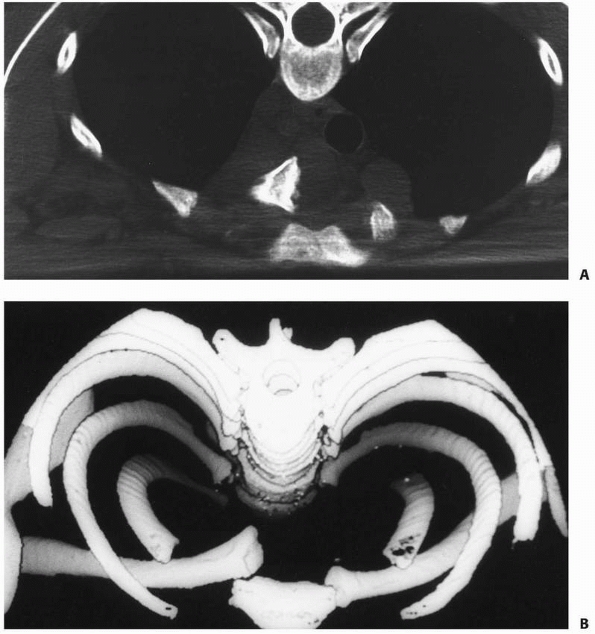

Currently, CT is the best method for evaluating injuries in the medial

third of the clavicle. Thin slice CT provides detailed information

about the morphology of the medial clavicle, the medial physis, the

degree of displacement, and possible injury to the underlying

intrathoracic structures (Fig. 17-4). Virtually

FIGURE 17-4 A. CT image of the clavicle showing posterior retrosternal dislocation of the medial end of the clavicle. B. Three-dimensional reconstruction of image shown in A.